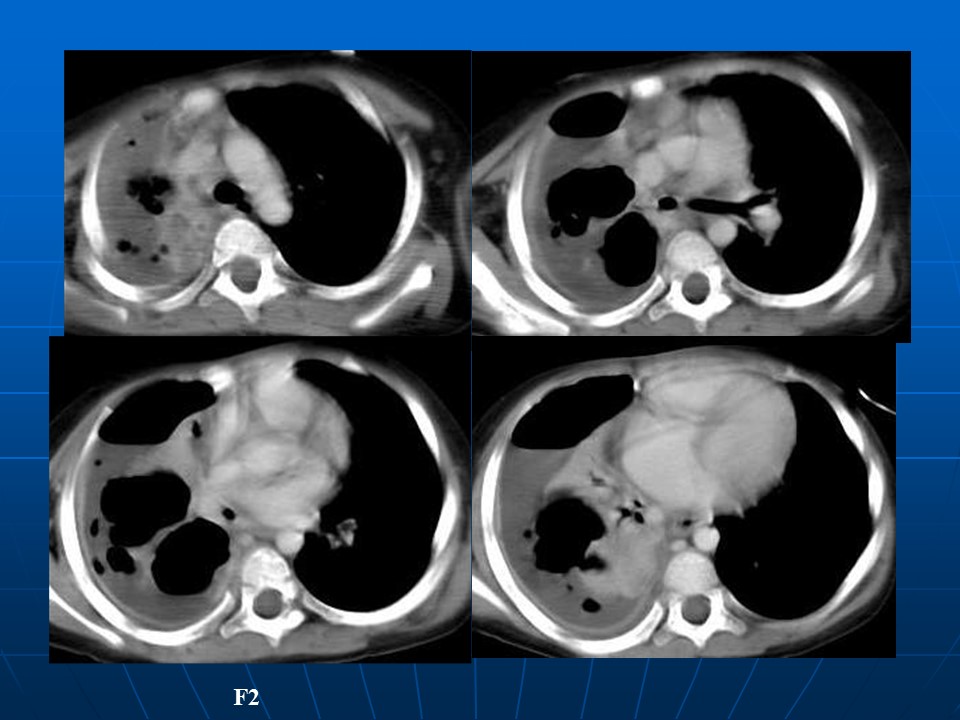

【病例】矽肺1例CT影像表现